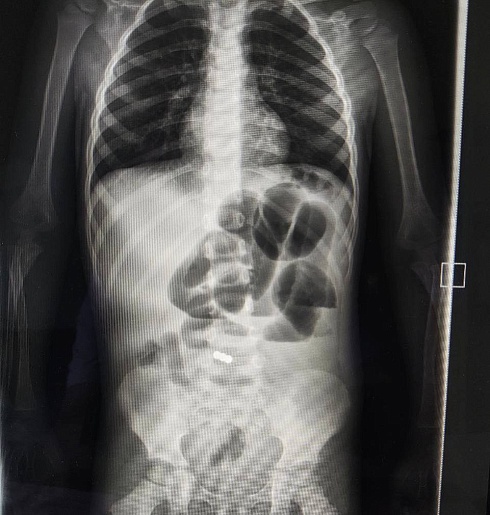

В детскую областную больницу поступил 2-летний ребенок в тяжелом состоянии: высокая температура, рвота, боли в животе. Диагностика выявила у малыша инородные тела в желудочно-кишечном тракте. Оказалось, ребенок проглотил магниты.

— У малыша участок подвздошной кишки с двумя магнитами примагнитился к куполу слепой кишки. Через червеобразный отросток и поврежденную стенку подвздошной кишки магниты были удалены. Также во время операции мы обнаружили врождённую аномалию кишечника — дивертикул Меккеля, который был удален. Это мешковидное выпячивание тонкой кишки, которое присутствует у некоторых детей с рождения. При воспалении дивертикул Меккеля может послужить причиной его перфорации в свободную брюшную полость с развитием перитонита, — рассказал Якоб Горбачев.